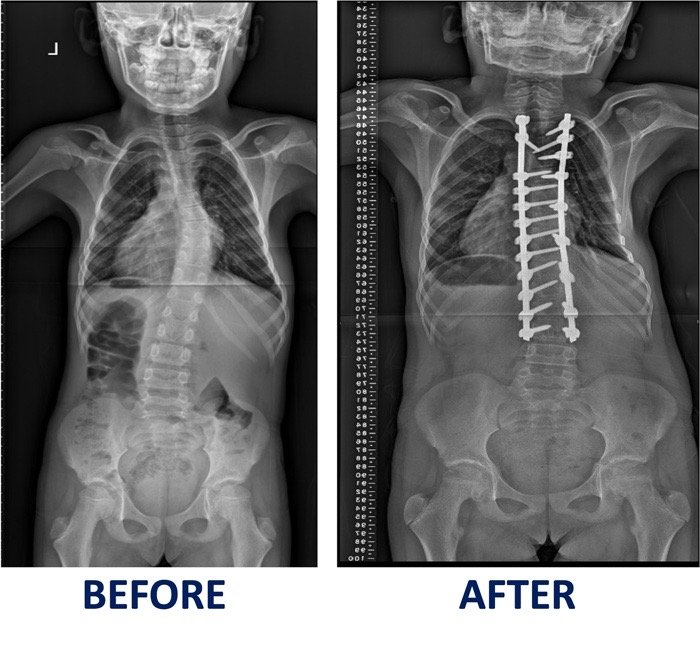

Scoliosis

In the heart of Kumasi, Ghana, a young girl named Mary embraced life with boundless energy. However, at just five years old, her parents noticed a concerning deformity that began to alter her childhood. Determined to find answers, they sought medical help at Komfo Anokye Teaching Hospital. Their search for a solution eventually led them to FOCOS Hospital in 2020, where they received a glimmer of hope—Mary’s condition could be corrected through surgery.

Despite the challenges ahead, her family remained steadfast, trusting in the kindness of others. Their prayers were answered in December 2021 when FOCOS GALA (2023) stepped forward to fully fund Mary’s surgery. It was a moment of immense relief and joy. By November 2024, she was admitted to FOCOS Hospital, where she underwent a successful surgery with no complications.

Today, Mary stands tall and strong, her life transformed. No longer defined by her condition, she walks forward with confidence and a bright future ahead.